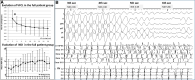

Methods and results: We evaluated 54 patients (50 ± 16 years) with VF in the setting of ischaemic (n = 15), hypertrophic (n = 8) or dilated cardiomyopathy (n = 12), or Brugada syndrome (n = 19). Ventricular fibrillation was mapped using body-surface mapping to identify driver (reentrant and focal) areas and invasive Purkinje mapping. Purkinje drivers were defined as Purkinje activities faster than the local ventricular rate. Structural substrate was delineated by electrogram criteria and by imaging. Catheter ablation was performed in 41 patients with recurrent VF. Sixty-one episodes of spontaneous (n = 10) or induced (n = 51) VF were mapped. Ventricular fibrillation was organized for the initial 5.0 ± 3.4 s, exhibiting large wavefronts with similar cycle lengths (CLs) across both ventricles (197 ± 23 vs. 196 ± 22 ms, P = 0.9). Most drivers (81%) originated from areas associated with the structural substrate. The Purkinje system was implicated as a trigger or driver in 43% of patients with cardiomyopathy. The transition to disorganized VF was associated with the acceleration of initial reentrant activities (CL shortening from 187 ± 17 to 175 ± 20 ms, P < 0.001), then spatial dissemination of drivers. Purkinje and substrate ablation resulted in the reduction of VF recurrences from a pre-procedural median of seven episodes [interquartile range (IQR) 4-16] to 0 episode (IQR 0-2) (P < 0.001) at 56 ± 30 months.

Conclusions: The onset of human VF is sustained by activities originating from Purkinje and structural substrate, before spreading throughout the ventricles to establish disorganized VF. Targeted ablation results in effective reduction of VF burden.